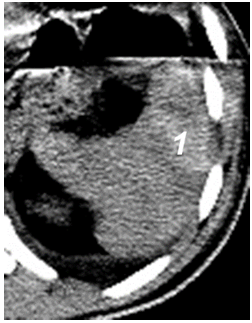

Ушибы селезенки сопровождаются интерстициальным отеком и геморрагическим пропитыванием тканей. Прямыми эхографическими признаками в первые 3–5 часов после травмы являются снижение эхогенности паренхимы и четкости контура органа, а также «разреженность» эхоструктуры паренхимы. Геморрагическое пропитывание паренхимы манифестировало наличием гиперэхогенных зон с нечеткими размытыми контурами в области повреждения (рис. 1). Характерно увеличение размеров всей селезенки или преимущественно поврежденного сегмента с нарушением ее конфигурации. Результаты цветового допплеровского картирования свидетельствуют о снижении кровотока, степень которого коррелирует с выраженностью эхографических проявлений отека паренхимы.

Рис. 1. Ушиб селезенки. Зона геморрагического пропитывания указана стрелками.